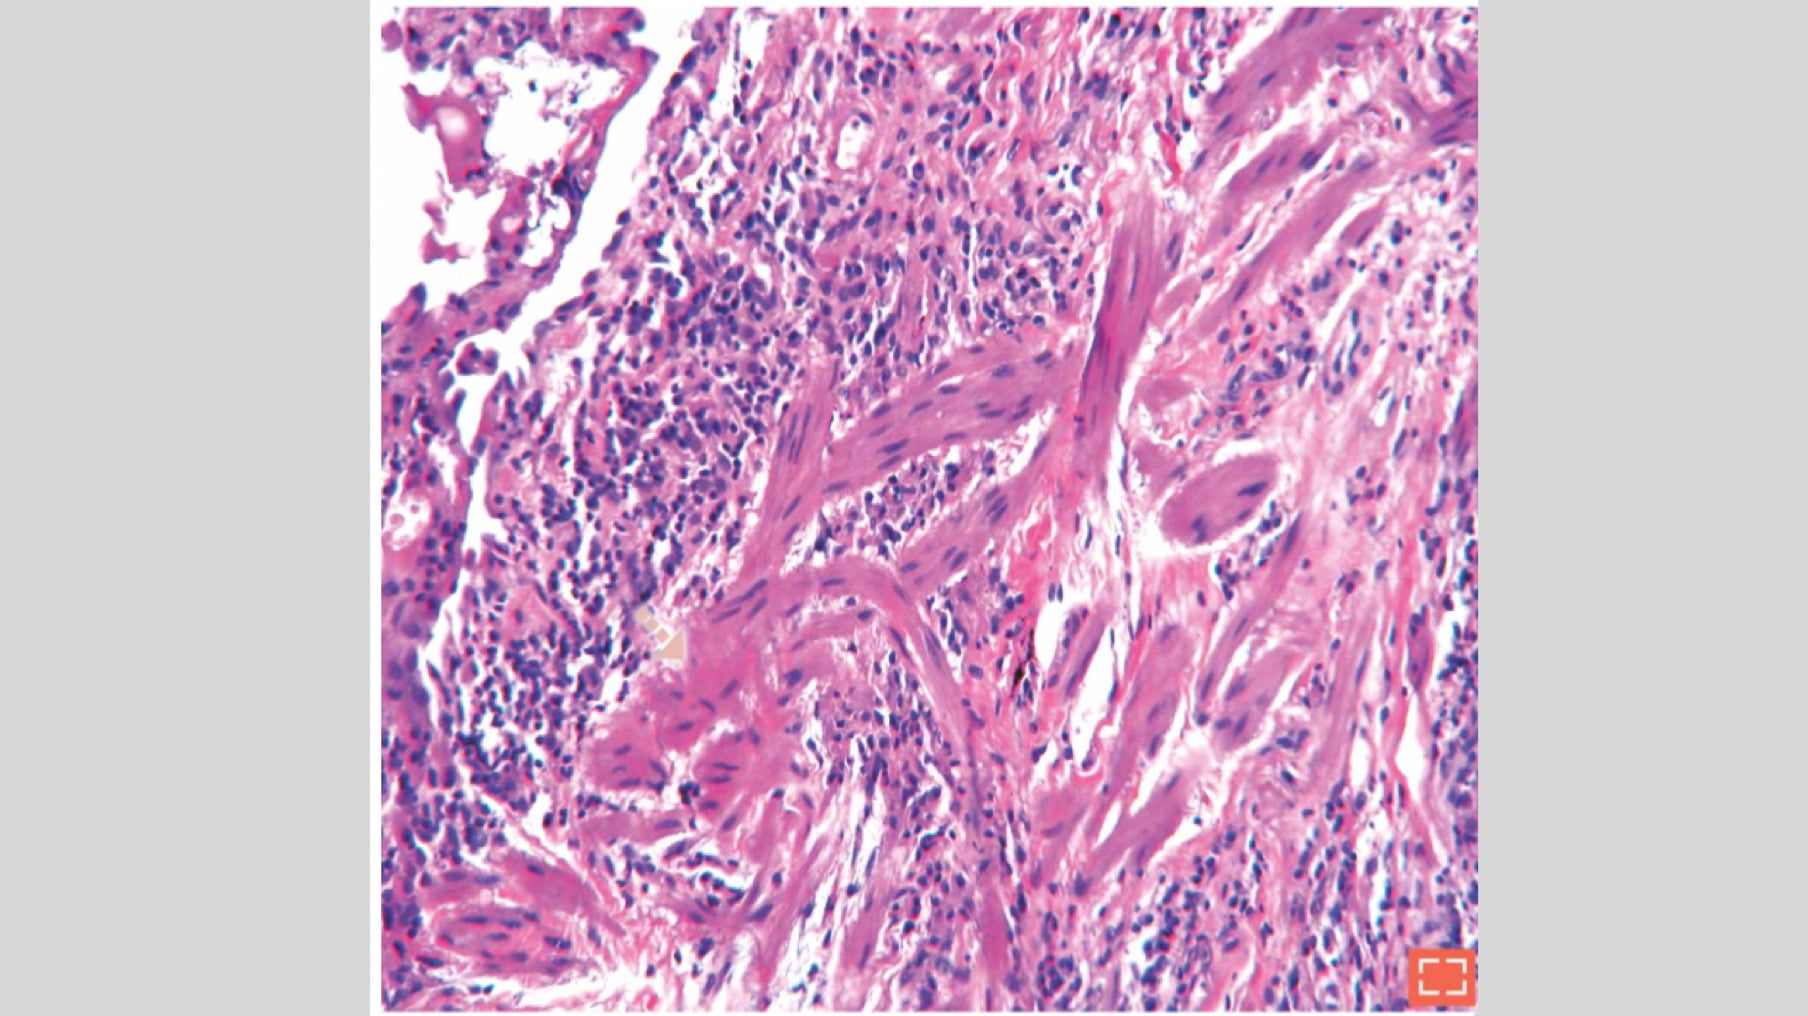

Bundles of hyperplastic smooth muscles

Synonyms: “myomatosis”, “muscular cirrhosis”

Destruction of the normal alveolar structure by fibrosis